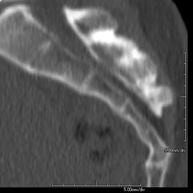

- Ear CT

Radiological test that provides high definition anatomical images of the ear (internal and external auditory canal, eardrum, ossicles of the ear), using CT (Computed Tomography) equipment. Indicated for: hearing disorders, vertigo, dizziness, tinnitus (ringing).

- Temporal bone CT

Radiological test that provides high definition anatomical images of the temporal bone (inner, middle and outer ear) using CT (Computed Tomography) equipment. Indicated for: sudden or chronic hearing loss, vertigo, dizziness, congenital malformations.